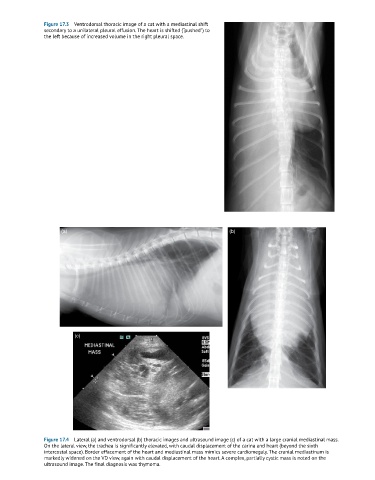

Figure 17.3 Ventrodorsal thoracic image of a cat with a mediastinal shift

secondary to a unilateral pleural effusion. The heart is shifted (“pushed”) to

the left because of increased volume in the right pleural space.

Figure 17.4 Lateral (a) and ventrodorsal (b) thoracic images and ultrasound image (c) of a cat with a large cranial mediastinal mass.

On the lateral view, the trachea is significantly elevated, with caudal displacement of the carina and heart (beyond the sixth

intercostal space). Border effacement of the heart and mediastinal mass mimics severe cardiomegaly. The cranial mediastinum is

markedly widened on the VD view, again with caudal displacement of the heart. A complex, partially cystic mass is noted on the

ultrasound image. The final diagnosis was thymoma.